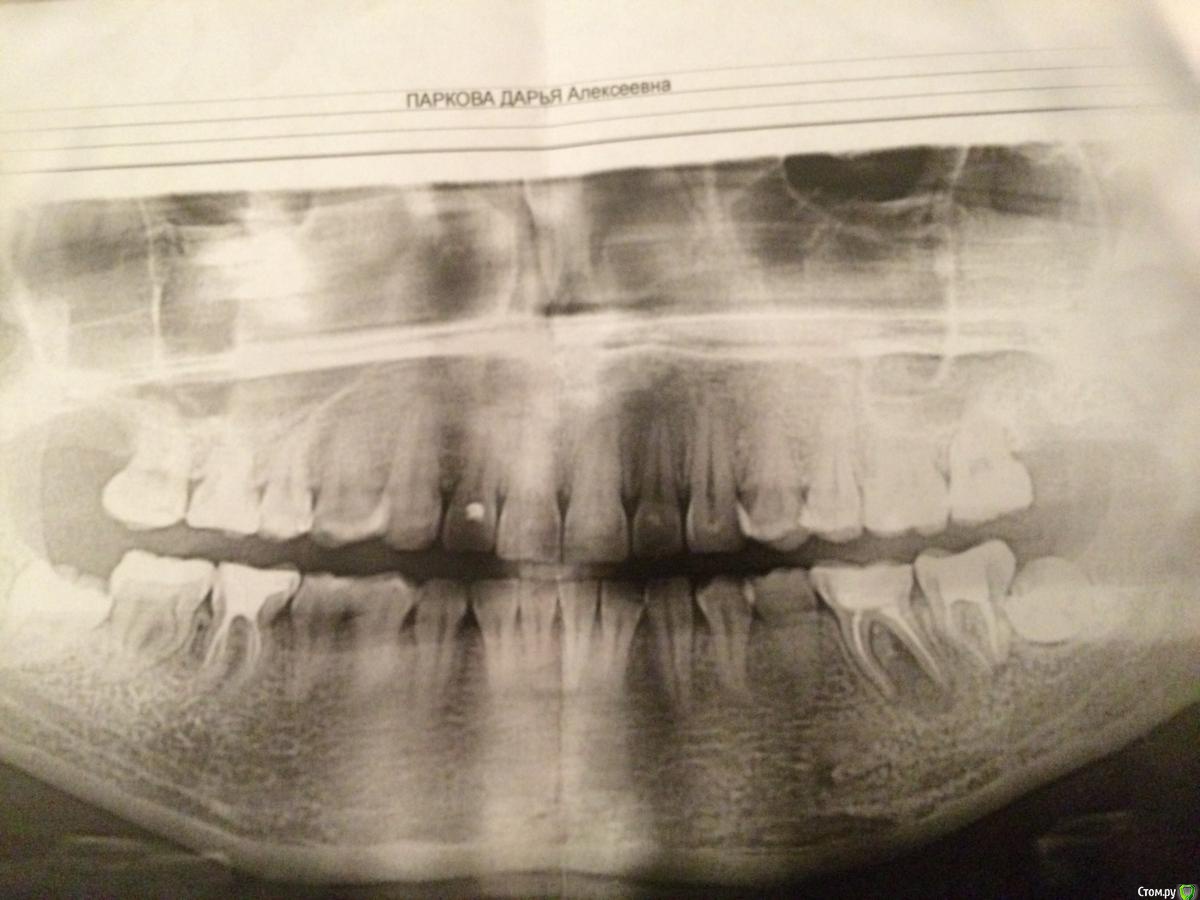

Dariadaria Опубликовано 13 сентября, 2015 Поделиться Опубликовано 13 сентября, 2015 Здравствуйте, дорогие! Обнаружили у меня большую кисту зуба. Хирург сказал, что надо удалять зуб с кистой, терапевт посоветовал попробовать сохранить зуб и лечить терапевтическими методами. Зуб стало жалко, поэтому решила попробовать вылечить. Терапевт что-то с этим зубом делал, не знаю что точно, поставил временную пломбу, через пару недель снова что-то делали, чистил каналы, потом вложил пасту(с содержанием йода, и привкус йода во рту присутствовал иногда в течение месяца), поставил пломбу, сказал через три месяца прийти. Интересно ваше мнение, как считаете, можно ли вылечить такую кисту или всё равно придется удалять? Поделитесь опытом)))Зуб шестерка слева(на снимке получается справа, вы это знаете, конечно, но на всякий случай Ссылка на комментарий

Dariadaria Опубликовано 13 сентября, 2015 Автор Поделиться Опубликовано 13 сентября, 2015 Вот снимок Ссылка на комментарий